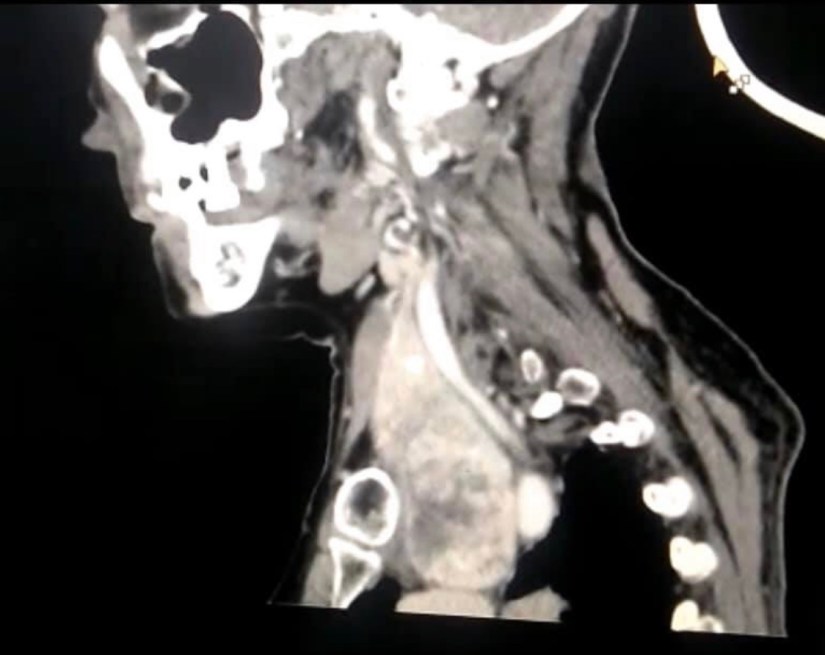

CT Scanning is Indicated for Retrosternal Goiter

• CT scanning is indicated for retrosternal goiter and can provideinformation on the following:

• Confirmation of the presence and determination of extent of retrosternal extension

• A ‘road map’ for the anesthetist:

• Tracheal deviation and compression

• Esophageal compression

• At-risk anatomical structures in the impending surgical field

• An assessment of malignancy (not accessible by ultrasound)

• Anterior versus posterior mediastinal extension

• The likelihood that the goiter can be extracted without the need for a sternotomy:

• The ‘shape’ of the goiter